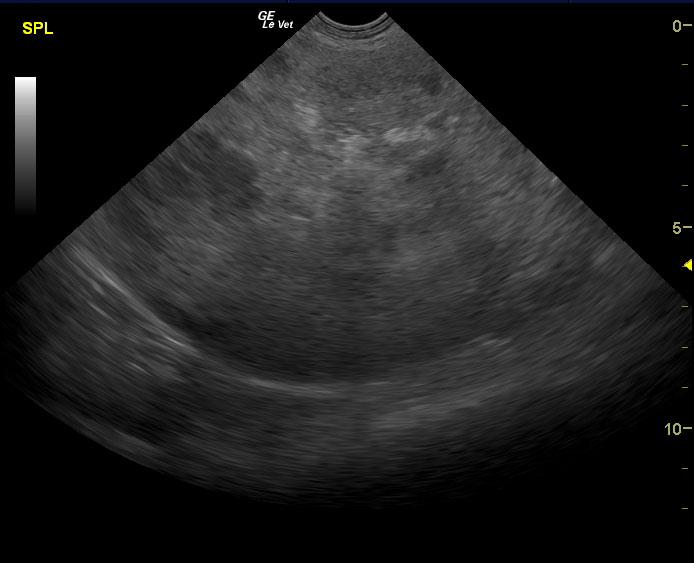

A 14-year-old SF Chow mix was presented for evaluation of weakness, which had also been present a week ago. On physical examination, a palpable abdominal mass was present. Severe non-regenerative anemia and hypoalbuminemia were present on CBC and blood chemistry.